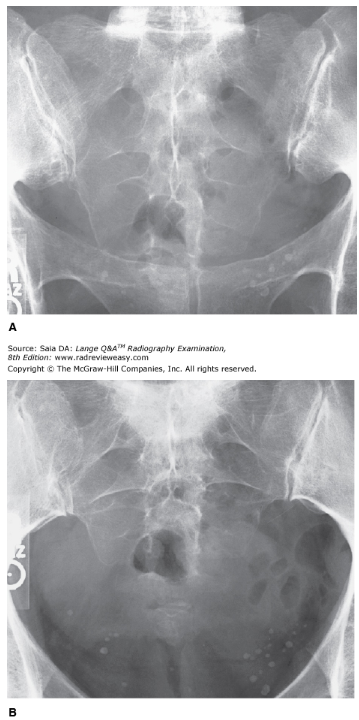

Which of the following statements is (are) correct with respect to the images shown in Figure 2–23?

A - 1 only

There are five fused sacral vertebrae; the fused transverse processes form the alae. The anterior and posterior sacral foramina transmit spinal nerves. The sacrum articulates superiorly with the fifth lumbar vertebra, forming the L5–S1 articulation, and inferiorly with the coccyx, forming the sacrococcygeal joint. The sacrum curves posteriorly and inferiorly, whereas the coccyx curves anteriorly; thus, they require different tube angles to “open them up.” Image A demonstrates an AP axial projection of the sacrum with a central ray angulation of 15 degrees cephalad. Image B is an AP axial projection of the coccyx using the required 10-degree caudal central ray angle.